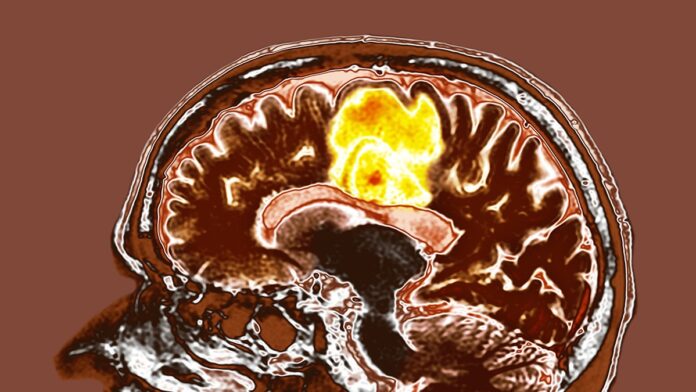

Wstępne badanie przeprowadzone w szpitalu Tata Memorial w Indiach sugeruje, że połączenie resweratrolu i miedzi może zaoferować nowe podejście do leczenia glejaka wielopostaciowego, jednej z najbardziej agresywnych postaci raka mózgu. Chociaż wstępne wyniki są zachęcające, naukowcy podkreślają, że potrzebne są długoterminowe dane, aby potwierdzić wpływ suplementów na przeżycie pacjentów.

Glejak wielopostaciowy jest niezwykle trudny w leczeniu ze względu na szybki wzrost i oporność na tradycyjne terapie. Obecne metody leczenia – chirurgia, radioterapia i chemioterapia – przedłużają życie, ale rzadko prowadzą do całkowitej remisji. To motywuje do poszukiwania innowacyjnych strategii, w tym badania potencjału łatwo dostępnych związków, takich jak resweratrol i miedź.